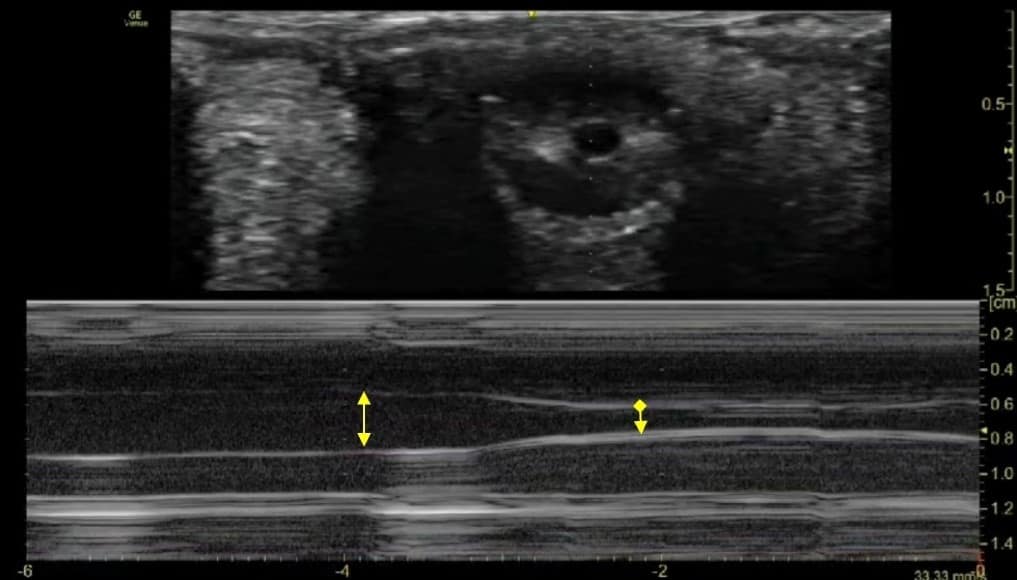

- B mode: Consensual PLR can be recorded as a series of coronal or para-sagittal images of the iris over a period of time (Figure 11 and Video 2).

- M mode: M-mode graphs corresponding to B scans can be acquired to demonstrate the pupillary diameter versus time (Figure 11 and Video 2). This allows analysis of the fine detail of the iris constriction.

The pupil is first displayed in the centre of the screen. A clear M mode display is obtained. The image of the pupil is then recorded while performing direct and consensual PLR using M mode. The frozen M-mode ultrasound images are stored.

- The maximum and minimum pupillary diameter at rest and at light reflex are marked using the built-in measurement tool in the ultrasonic system.

- The pupillary contraction time (PCT-defined as the time interval between the maximum and minimum PD during the process of light reflex) is calculated using the still images recorded with the ultrasound.

A single pupillary diameter assessment is obtained by the use of calliper-based measurement on a frozen image of the ultrasound scan. This may lead to inaccurate results with variation in pupil size. Ultrasound assessment has the advantage of easy repeatability and reproducibility, which averages out any small difference in pupillary diameters.29 On the M-mode strip, the superior-to-inferior diameter of the pupil is represented as a black band across the strip (Figure 11).